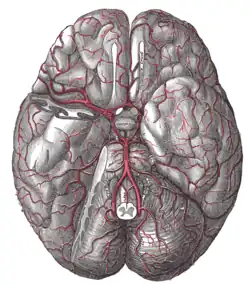

Tętnica podstawna (łac. arteria basilaris) – w anatomii człowieka pojedyncza tętnica powstająca z połączenia obu tętnic kręgowych. Biegnie w bruździe podstawnej mostu, na swoim przebiegu oddając liczne drobne gałęzie, a następnie w dole międzykonarowym dzieli się na tętnice tylne mózgu. Jej gałęzie unaczyniają m.in. płaty potyliczne i skroniowe mózgu, most, móżdżek oraz ucho wewnętrzne. Rozgałęzienie końcowe tętnicy podstawnej jest elementem koła tętniczego mózgu[1][2].

Nieparzystą tętnicę podstawną tworzą obie tętnice kręgowe łącząc się na stoku kości potylicznej[3]. Tętnica biegnie ku górze, pośrodkowo (tylko u 15–25% osób w linii prostej, z wiekiem wygina się bocznie od płaszczyzny pośrodkowej[4]) w bruździe podstawnej mostu, ku jego górnemu brzegowi, gdzie dzieli się na gałęzie końcowe – tętnice tylne mózgu[3]. Jej długość odpowiada wymiarowi powierzchni brzusznej mostu w płaszczyźnie pośrodkowej[5].

- Tętnice tylne mózgu – gałęzie końcowe, rozchodzące się pod tępym kątem od końca tętnicy podstawnej. Biegną do przodu od tętnic górnych móżdżku (rozdzielone od nich nerwami okoruchowymi, nerwami bloczkowymi i namiotem móżdżku), a następnie owijają się wokół konarów mózgu i wstępują na dolną powierzchnię płatów potylicznych. Tutaj tętnice rozgałęziają się unaczyniając płaty potyliczne i część płatów skroniowych, zespalają się z rozgałęzieniami tętnic przednich i środkowych. Na przebiegu przez istotę dziurkowaną tylną tętnice tylne mózgu oddają gałęzie unaczyniające jądra tylne mózgu oraz gałęzie do splotu naczyniówkowego komory trzeciej. Do początkowych odcinków tętnic tylnych mózgu dochodzą ponadto tętnice łączące tylne. Tym samym tętnice i rozgałęzienie, w którym mają początek, są elementami koła tętniczego mózgu[1][10].